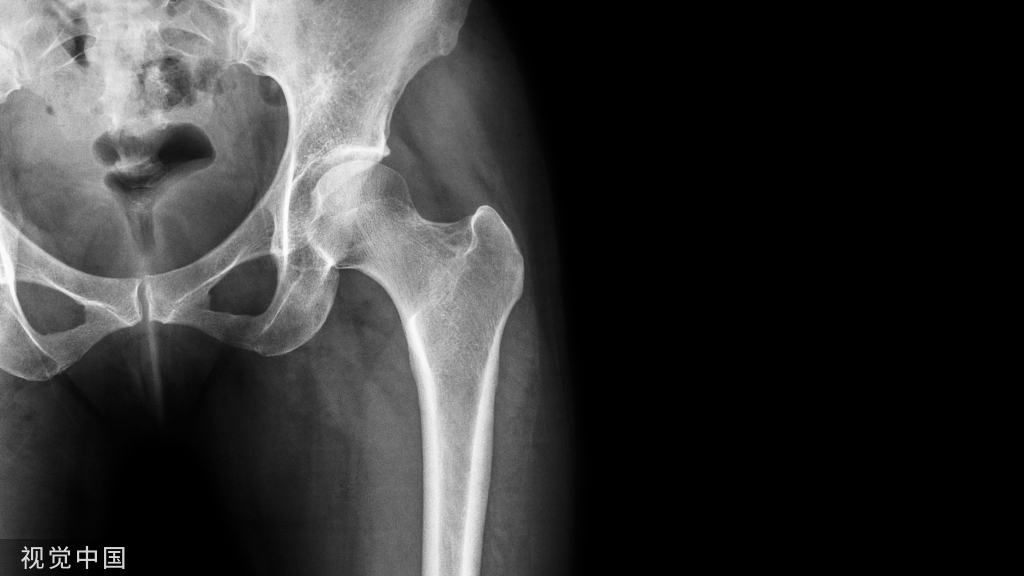

胫骨 pilon 骨折的发生多是由于高能量轴向负荷产生的关节和干骺端粉碎以及广泛的软组织损伤。腓骨骨折的存在是胫骨 pilon 骨折放射学严重程度的预测指标。

尽管 Ruedi 和 Allgower 于 1969 年提出手术治疗应首先固定腓骨以恢复长度,然后再固定胫骨,包括重建胫骨关节面,然后植骨等,但尚无明确的方案来建议固定的顺序和方法填补干骺端缺损和内侧支撑。

然而 ,关于胫骨pilon ORIF 中腓骨固定的作用报道不多,但越来越多的证据表明,在这些复杂骨折中,腓骨根本不需要固定。